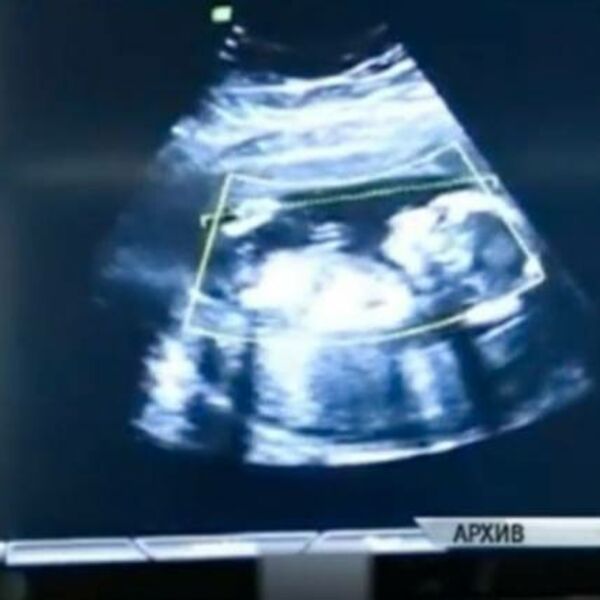

Ona je rođena sa srcem koje se nalazilo izvan grudnog koša, nečim što nije nikad preživela nijedna beba rođena u Velikoj Britaniji

Njen dolazak na svet nije bio ispunjen srećom i osmesima, već tugom i brigom. Ona je rođena sa srcem koje se nalazilo izvan grudnog koša, nečim što nije nikad preživela nijedna beba rođena u Velikoj Britaniji.